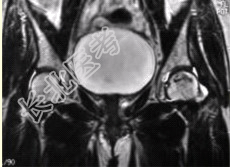

- [材料题] 男性,47岁。左髋部疼痛及压痛6个月,“4”字试验阳性。左髋关节内、外旋活动受限。检查提示:左髋关节活动轻度受限,大腿上部轻压痛。血常规检查正常。髋关节CT及MRI如下图。

- 多项选择题1.根据髋关节CT和MR影像,你认为此病例的影像学表现有

A、CT检查未见异常

B、左侧股骨头内可见线样高密度影

C、左股骨头塌陷变扁,其内可见条带状硬化

D、左股骨头内见蜿蜒走行的T

、T

低信号条带影E、左髋关节腔内可见弧线状长T

、长T

信号F、左髋关节间隙变窄

- 多项选择题2.对本病例,你首先考虑的诊断是

B、左股骨头缺血性坏死

F、左髋关节腔积液